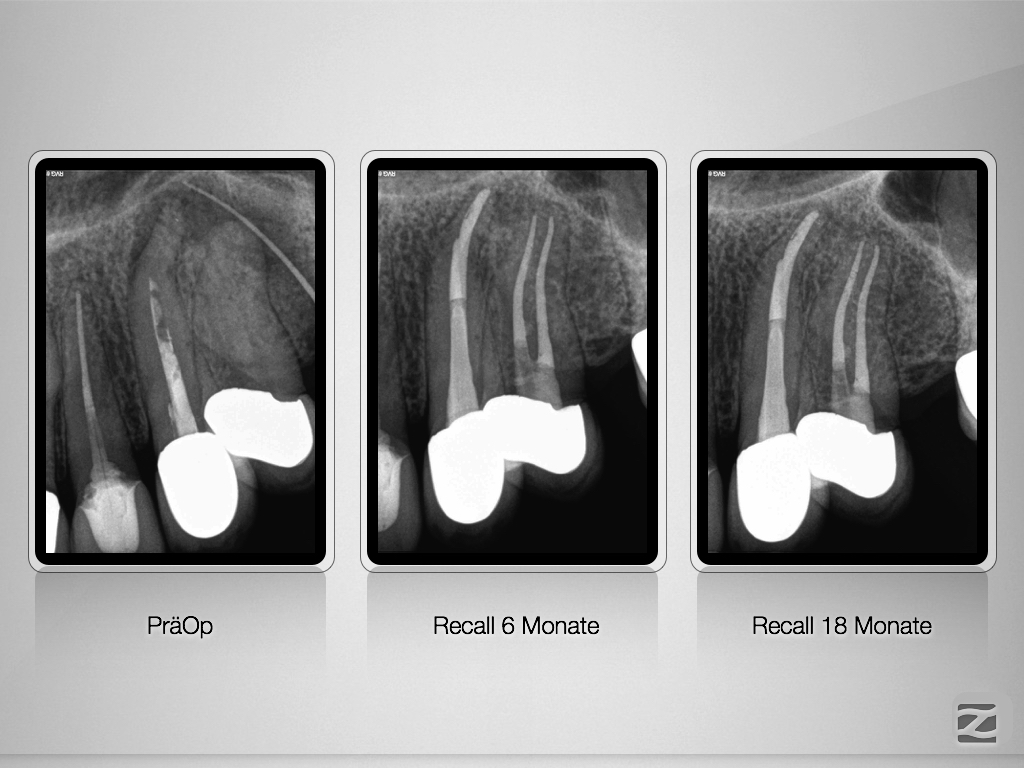

23 & 24 D.004

Ursache und Wirkung